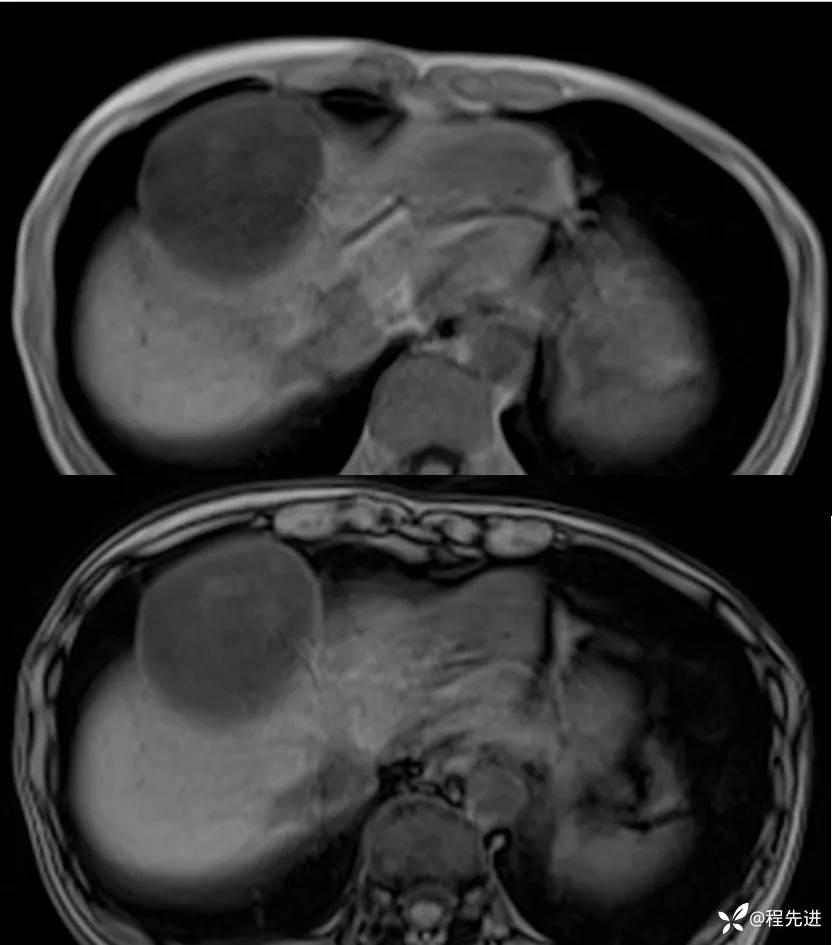

MRI平扫+增强: